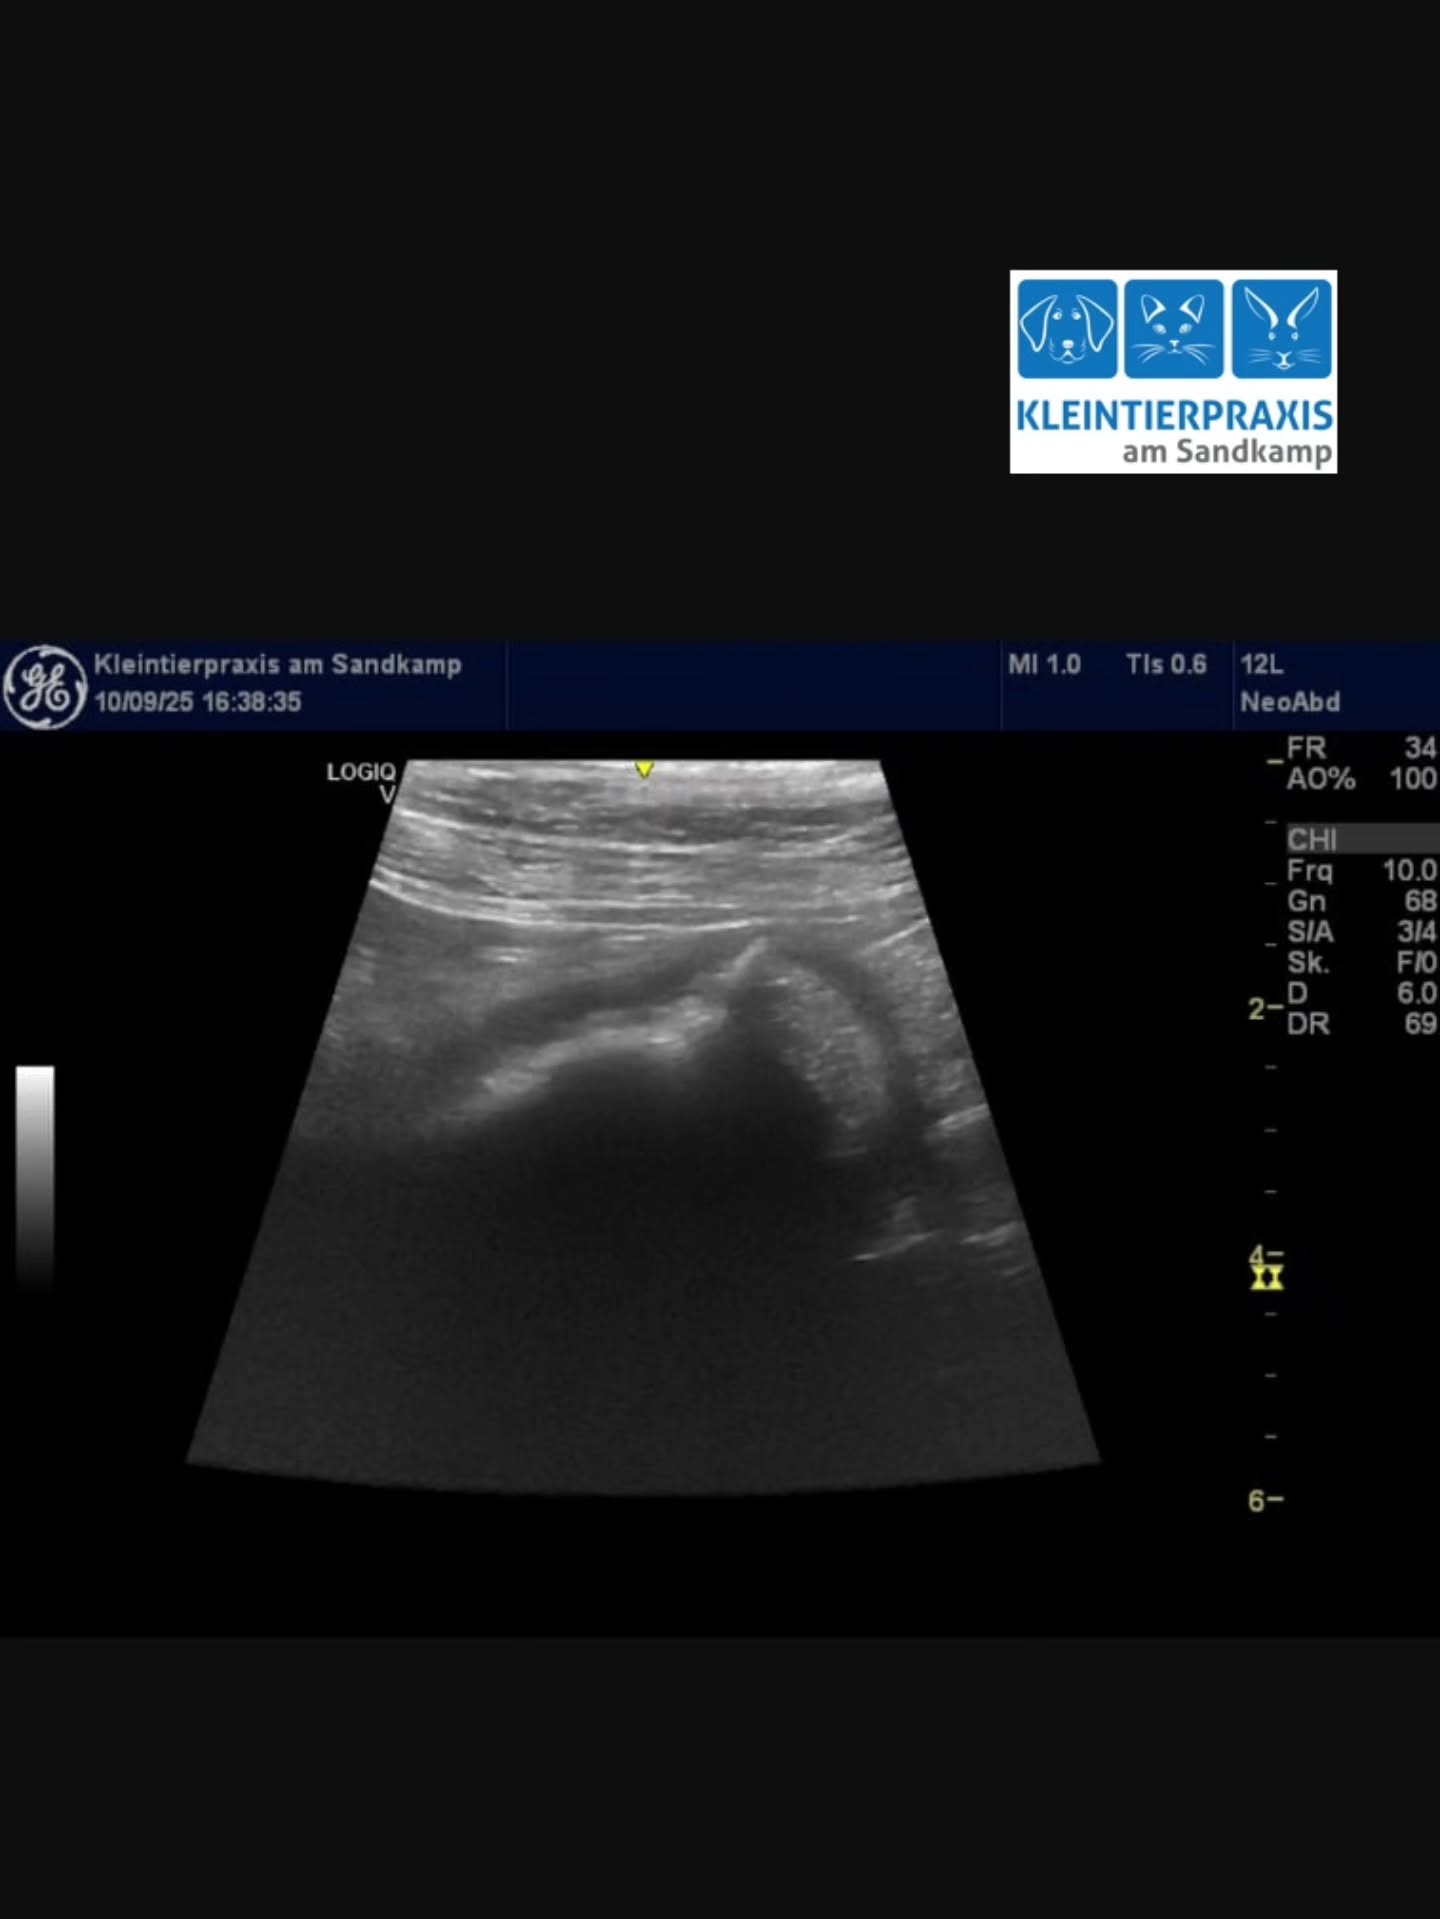

![Mr. Cat, ein 14 jähriger Kater, wurde uns vor 6 Monaten mit dem Verdacht auf ein bösartiges Sarkom an der linken Handwurzel (Vorderpfote [Carpus]) vorgestellt. Aufgrund der Aggressivität des Tumors musste der ganze Arm amputiert werden.

Mittlerweile ist alles gut verheilt. 🥰Mr. Cat kommt auf drei Beinen gut zurecht und ist gesund. 😻 Und am Wichtigsten: es ist kein weiterer Tumor aufgetaucht. 😁Nicht immer ist Krebs ein Todesurteil. Es lohnt sich immer zu kämpfen. 💪🏻